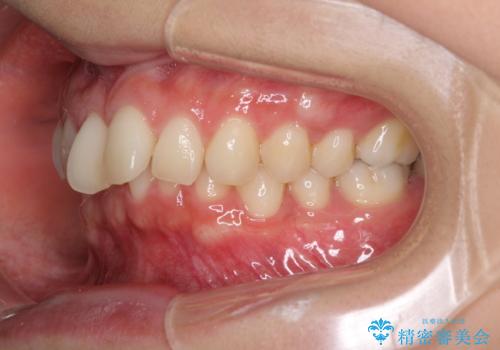

インビザラインによるディープバイトの改善

- 口元の前突感と深い咬み合わせ(ディープバイト)を気にして来院された患者様です。

インビザラインによる上下歯列の遠心移動(後方移動)と、それに伴う近心傾斜(前方傾斜)の改善により、口元の突出感とディープバイトを改善することとしました。

前歯のデコボコを最も気にしていましたが、咬み合わせが深く歯ぎしりが自由にできない点を指摘すると、常に食いしばってしまうことも悩みであることが分かりました。

咬合状態が大きく変化したため、治療後半では咬み合わせの位置が定まらなくなりました。上下の前歯に後戻り防止用のワイヤーを装着し、奥歯の咬合をフリーにしたことで1ヶ月ほどで咬み合わせが定まりました。